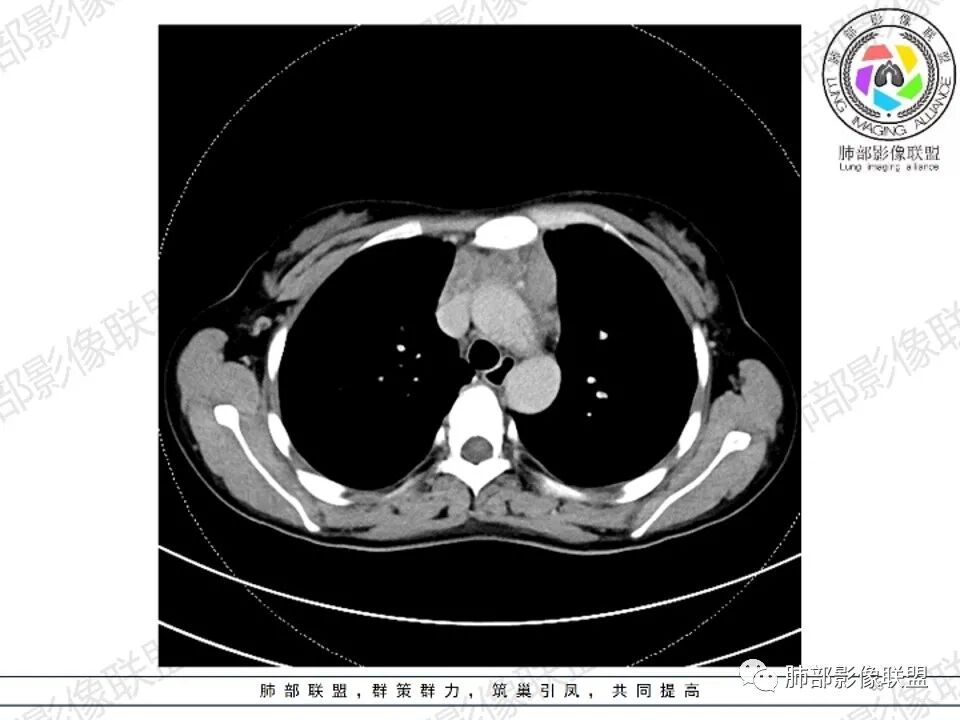

年轻女性,贫血,CT示前纵隔团片状软组织占位,多结节堆积感,塑形生长,边界欠清,包绕大血管及心包,增强明显不均匀强化,内见血管漂浮。纵隔4R,5,7区及双侧腋窝多发肿大淋巴结,综合考虑为淋巴瘤可能

前纵隔和双侧腋窝多发的淋巴结肿大,前纵隔为甚,融合呈中等强化,部分坏死呈低密度,包埋肺动脉主干和左心缘,融合斑块状,内见血管飘浮特点,前纵隔脂肪间隙混浊,首选淋巴瘤!

CT:定位纵膈病变,前中纵隔多发肿块,质软,塑形,密度不均匀,边界清楚。增强不均匀强化,坏死边界清楚,血管漂浮征。双侧腋下多组淋巴结肿大,明显异常强化。